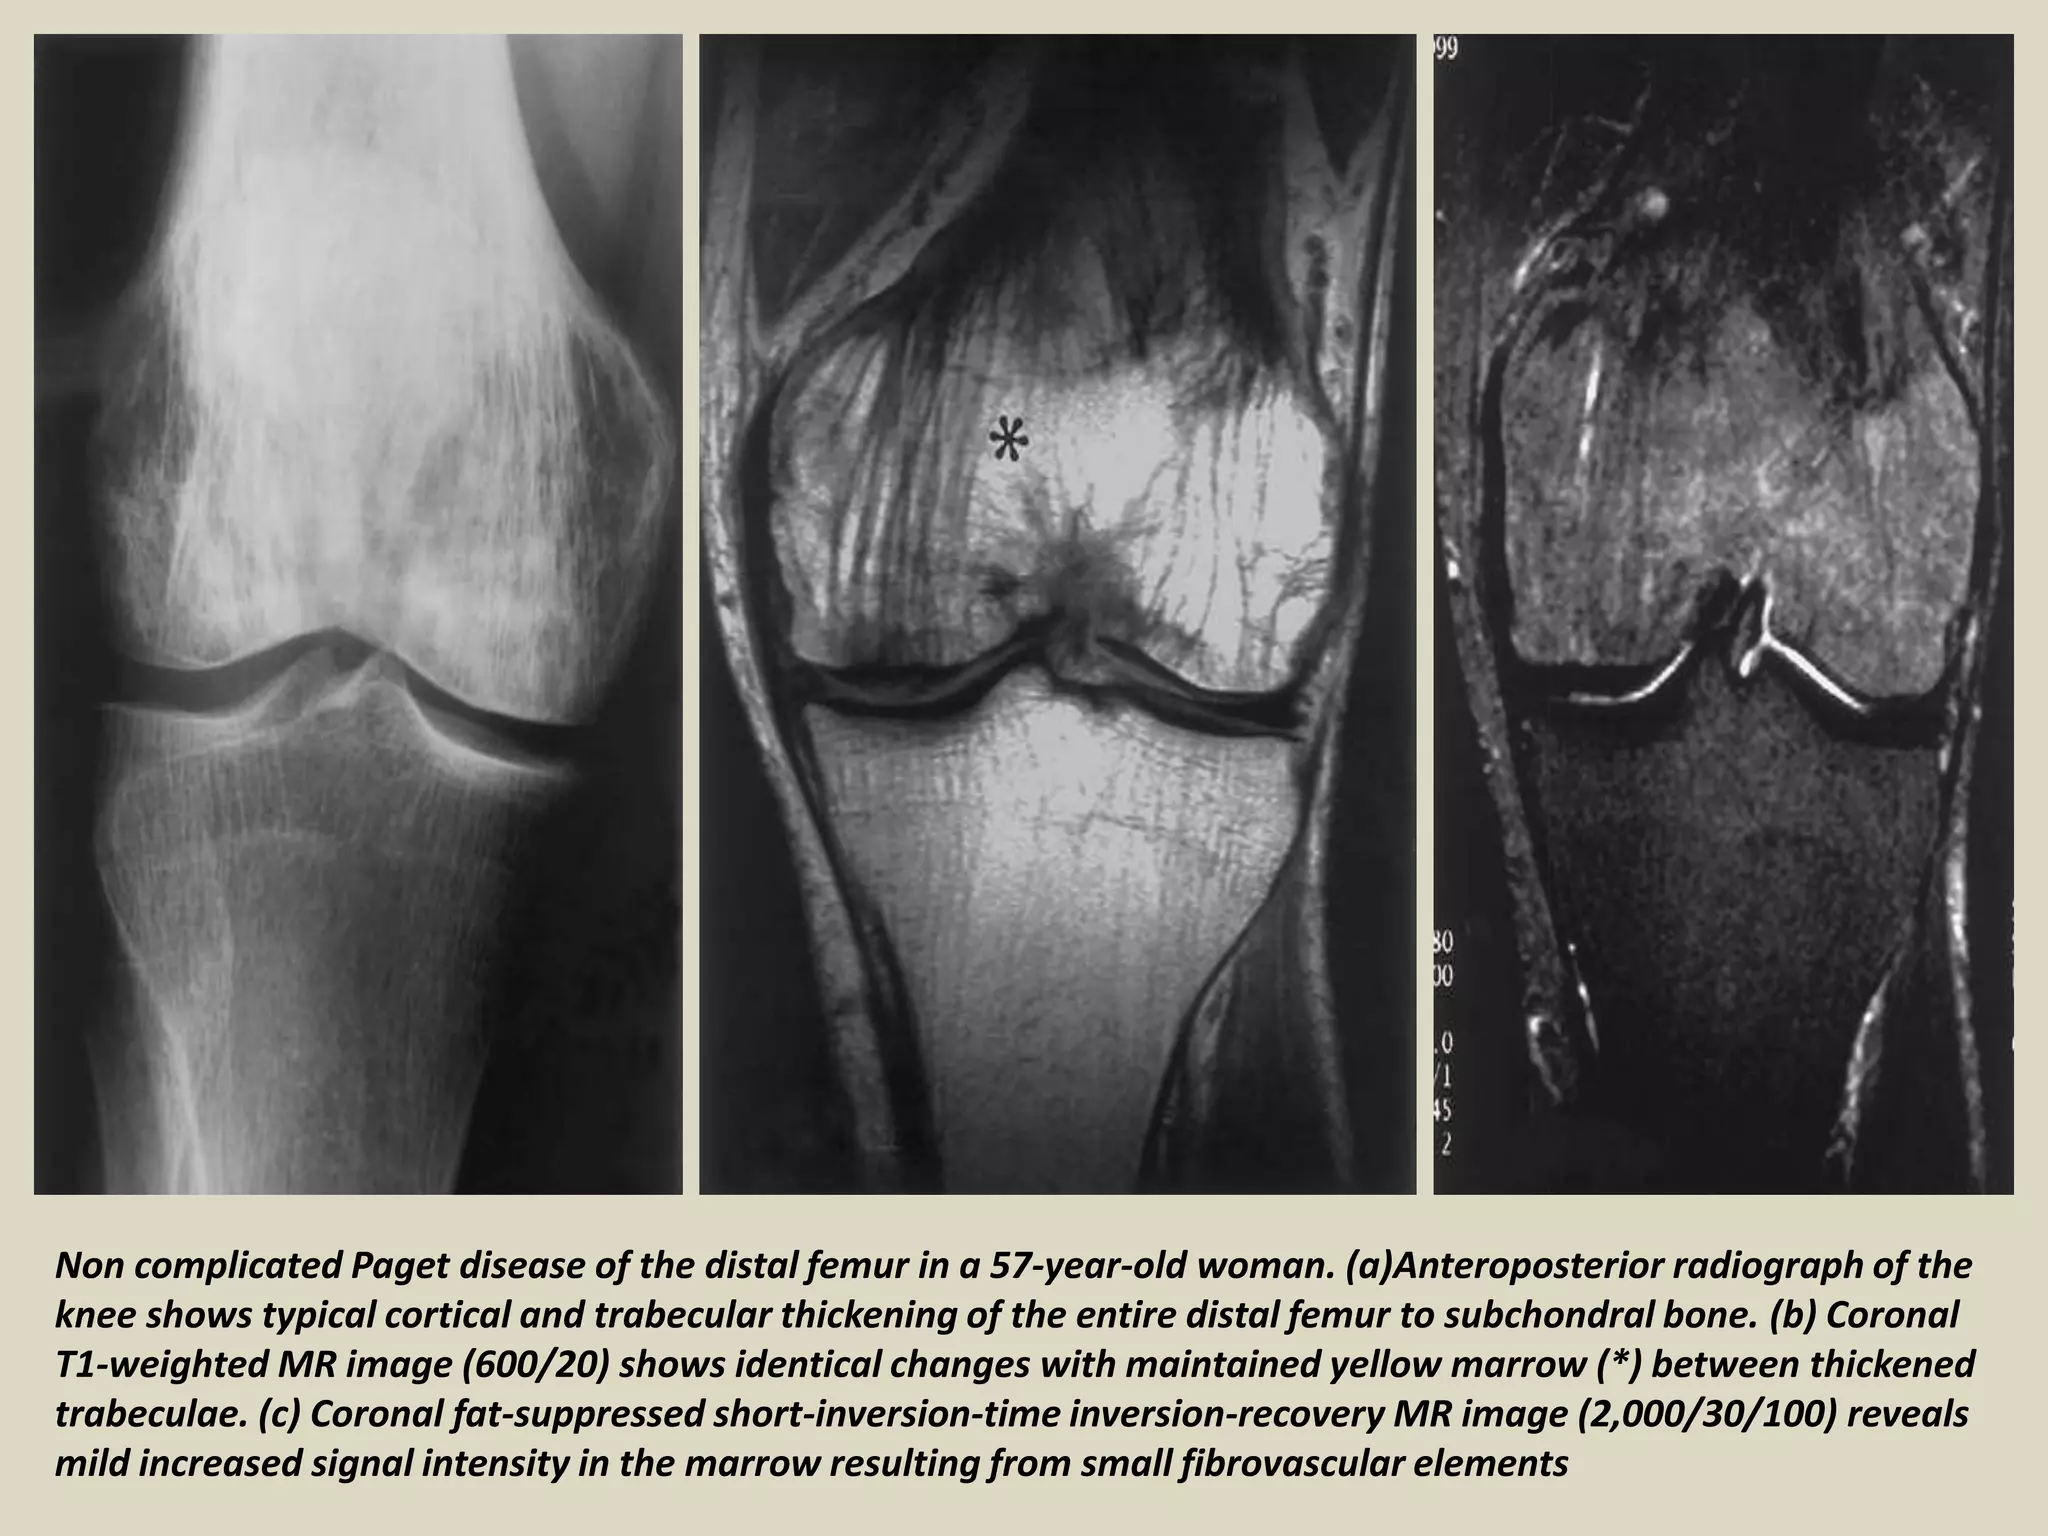

Non complicated Paget disease of the distal femur in a 57-year-old woman. (a)Anteroposterior radiograph of the

knee shows typical cortical and trabecular thickening of the entire distal femur to subchondral bone. (b) Coronal

T1-weighted MR image (600/20) shows identical changes with maintained yellow marrow (*) between thickened

trabeculae. (c) Coronal fat-suppressed short-inversion-time inversion-recovery MR image (2,000/30/100) reveals

mild increased signal intensity in the marrow resulting from small fibrovascular elements

Non complicated Pagetdisease of the distal femur in a 57-year-old woman. (a)Anteroposterior radiograph of the knee shows typical cortical and trabecular thickening of the entire distal femur to subchondral bone. (b) Coronal T1-weighted MR image (600/20) shows identical changes with maintained yellow marrow (*) between thickened trabeculae. (c) Coronal fat-suppressed short-inversion-time inversion-recovery MR image (2,000/30/100) reveals mild increased signal intensity in the marrow resulting from small fibrovascular elements